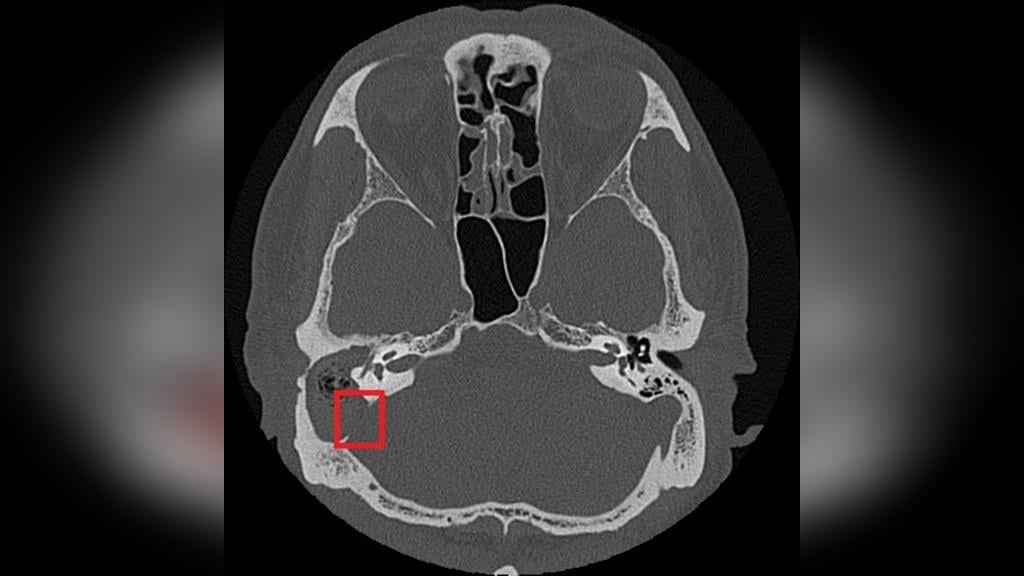

由於膽脂瘤多發生在中耳或接近顱底的位置,一旦形成,可能影響聽力與神經功能,其分泌物亦容易滋生細菌,導致反覆感染;若未及時治療,可能引發暈眩,甚至因鄰近顱內而造成腦膜炎、腦炎或腦膿瘍。目前,手術切除是膽脂瘤根治的唯一方法,術前需以顳骨電腦斷層檢查評估膽脂瘤範圍及侵蝕程度;手術方式依病灶大小、位置,可能採耳內微創、耳前或耳後切開術,徹底清除膽脂瘤並重建受損結構。

急性發炎期則需輔以抗生素控制感染,術後追蹤可降低復發風險,但膽脂瘤若已侵蝕骨質,仍需長期觀察。以張先生為例,雖前後接受過局部藥物、抗生素治療,但考量其慢性中耳炎併發膽脂瘤已破壞聽小骨、乳突及部分顱底骨質,因此需從耳後切開進入外耳道及中耳腔,打開耳後的乳突骨,將病變組織除去後,重建修復骨骼和軟組織缺口。